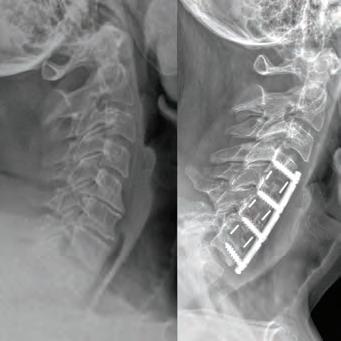

Stephen P. Courtney, MD

BOARD-CERTIFIED, FELLOWSHIP-TRAINED ORTHOPEDIC SPINE SURGEON PRACTICING FOR 26 YEARS.

For board-certifid, fellowship trained orthopedic spine surgeon

Dr. Stephen P. Courtney, patients come fist. It’s an ethos that developed early on in his life and one that has helped guide him in his journey to earn a distinguished reputation among his professional colleagues, medical peers and, most importantly, his patients.

Dr. Courtney’s residency at Texas A&M University Medical Center and further specialty training through a fellowship at Florida Neck & Back Institute in Gainesville, Florida, additionally cemented his strong medical foundation. From there, he continued to gain more knowledge and insight on how to help his patients with useful tools, while recognizing there was room for much improvement in the tools at hand.

Ths realization inspired Dr. Courtney to design, develop, biomechanically test, complete FDA testing and oversee quality control and

validation on a host of tools he created. To date, Dr. Courtney has developed nine spinal product lines and obtained nine patents and 14 trademarks on spine related products.

When he’s not traveling the country training other physicians on how to utilize his products, Dr. Courtney dedicates himself to the patients of his own medical practice, Advanced Spine Center.

Led by Dr. Courtney, the skilled team at Advanced Spine Center cares for patients with neck and back pain using a wide array of the most state-of-the-art tools and techniques—from conservative physical therapy and injection therapy—to advanced pain management, as well as surgical intervention. We employ the latest in minimally invasive spine surgeries, in addition to cutting-edge replacement technology. Incorporating both high tech and high touch, we get our valued patients back to their lives so they can enjoy all the activities they love.

SURGERY: C4/C5, C5/C6, C6/C7 ACF (ANTERIOR CERVICAL FUSION)

“Great medicine coupled with great care. Dr. Courtney takes the time to listen to your medical needs. He put me at ease regarding my condition.”